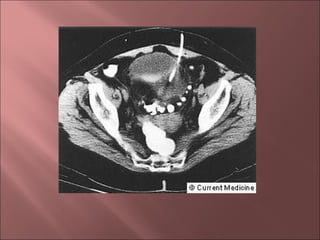

•TAC helicoidal

•Engrosamiento pared Intestinal

•Grasa mesentérica en franjas

•Abscesos

•ECO

•Engrosamiento pared colónica

•Masas